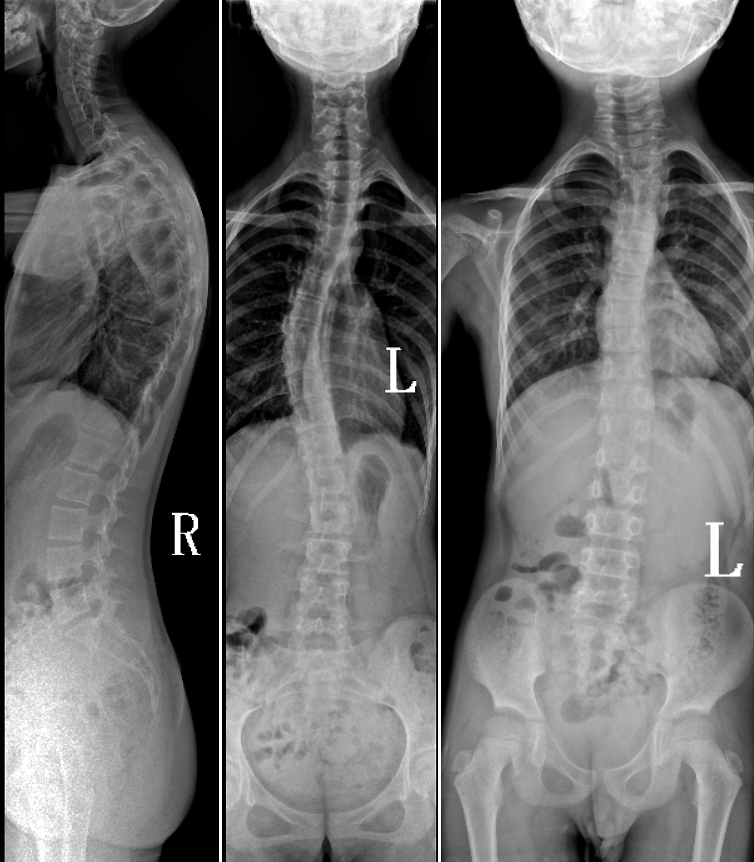

DR是臨床骨科的重要檢查手段之一。在骨科檢查中,脊柱矯形、長骨骨折、腰椎退行性病變等,需要采集脊柱、下肢全景圖像,輔助醫(yī)生臨床診斷,從而制定科學(xué)的治療方案,普愛醫(yī)療的大視野平板動態(tài)DR就像是一座橋梁,連接起現(xiàn)代醫(yī)療技術(shù)與當(dāng)?shù)厝嗣竦尼t(yī)療需求。

普愛醫(yī)療自主研發(fā)的大視野平板動態(tài),采用17"*34"的有效視野,一次曝光即可得到全脊柱或全下肢影像。相較于多張攝影再軟件拼接的DR設(shè)備,PLX8600解決了拼接圖像存在密度不均勻,拼接處圖像配準(zhǔn)和放大效應(yīng)等問題,給臨床帶來了真正的大視野影像解決方案。

除了常規(guī)靜態(tài)攝影外,PLX8600的大平板具備動態(tài)透視和點(diǎn)片功能,能夠很好地觀察復(fù)雜部位病灶,有效地抓取關(guān)鍵幀,降低患者多次攝片的概率。如:全脊柱狀態(tài)評估、長骨關(guān)節(jié)活動度、下肢靜脈造影瓣膜功能評估、消化道功能評估、脊髓造影等更多大視野臨床應(yīng)用,“多面手”都能輕松應(yīng)對。